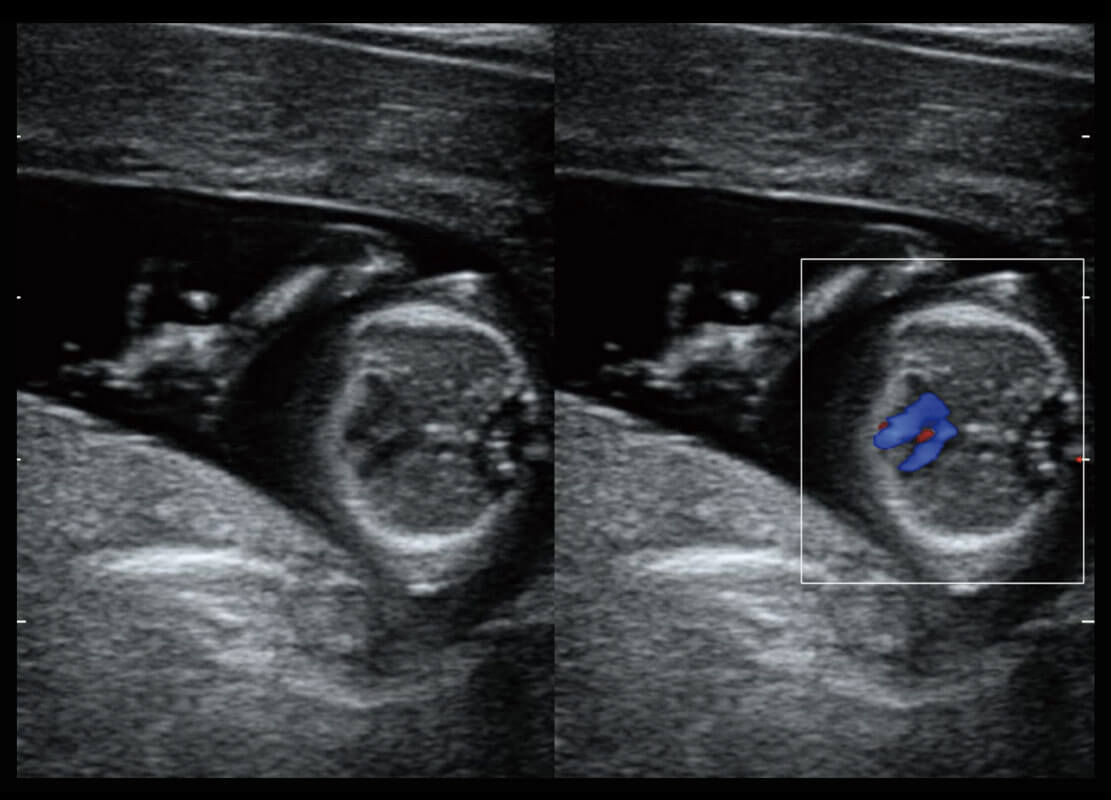

盆底超声

P60为盆底超声检查提供应用方案,多种腔内及腹部容积探头提供从二维、三维到四维的优异图像品质,实时快速三维容积数据获取,专业的测量工具包等人性化设计,为超声医生诊断提供有力保障。

Lev.Hiat A-r: 16.33 cm2

Lev.Hiat H-r: 53.70 mm

Lev.Hiat W-r: 43.96 mm

Lt-LUG-r: 24.16 mm

Rt-LUG-r: 19.94 mm

S-Pelvic

能够简化盆底检查的操作流程,可在二维模式及三维成像模式下实现一键自动提取出标准切面、自动识别当前切面、自动测量,提升盆底检查的高效性,同时也能让青年医生快捷的获得准确的检查结果。